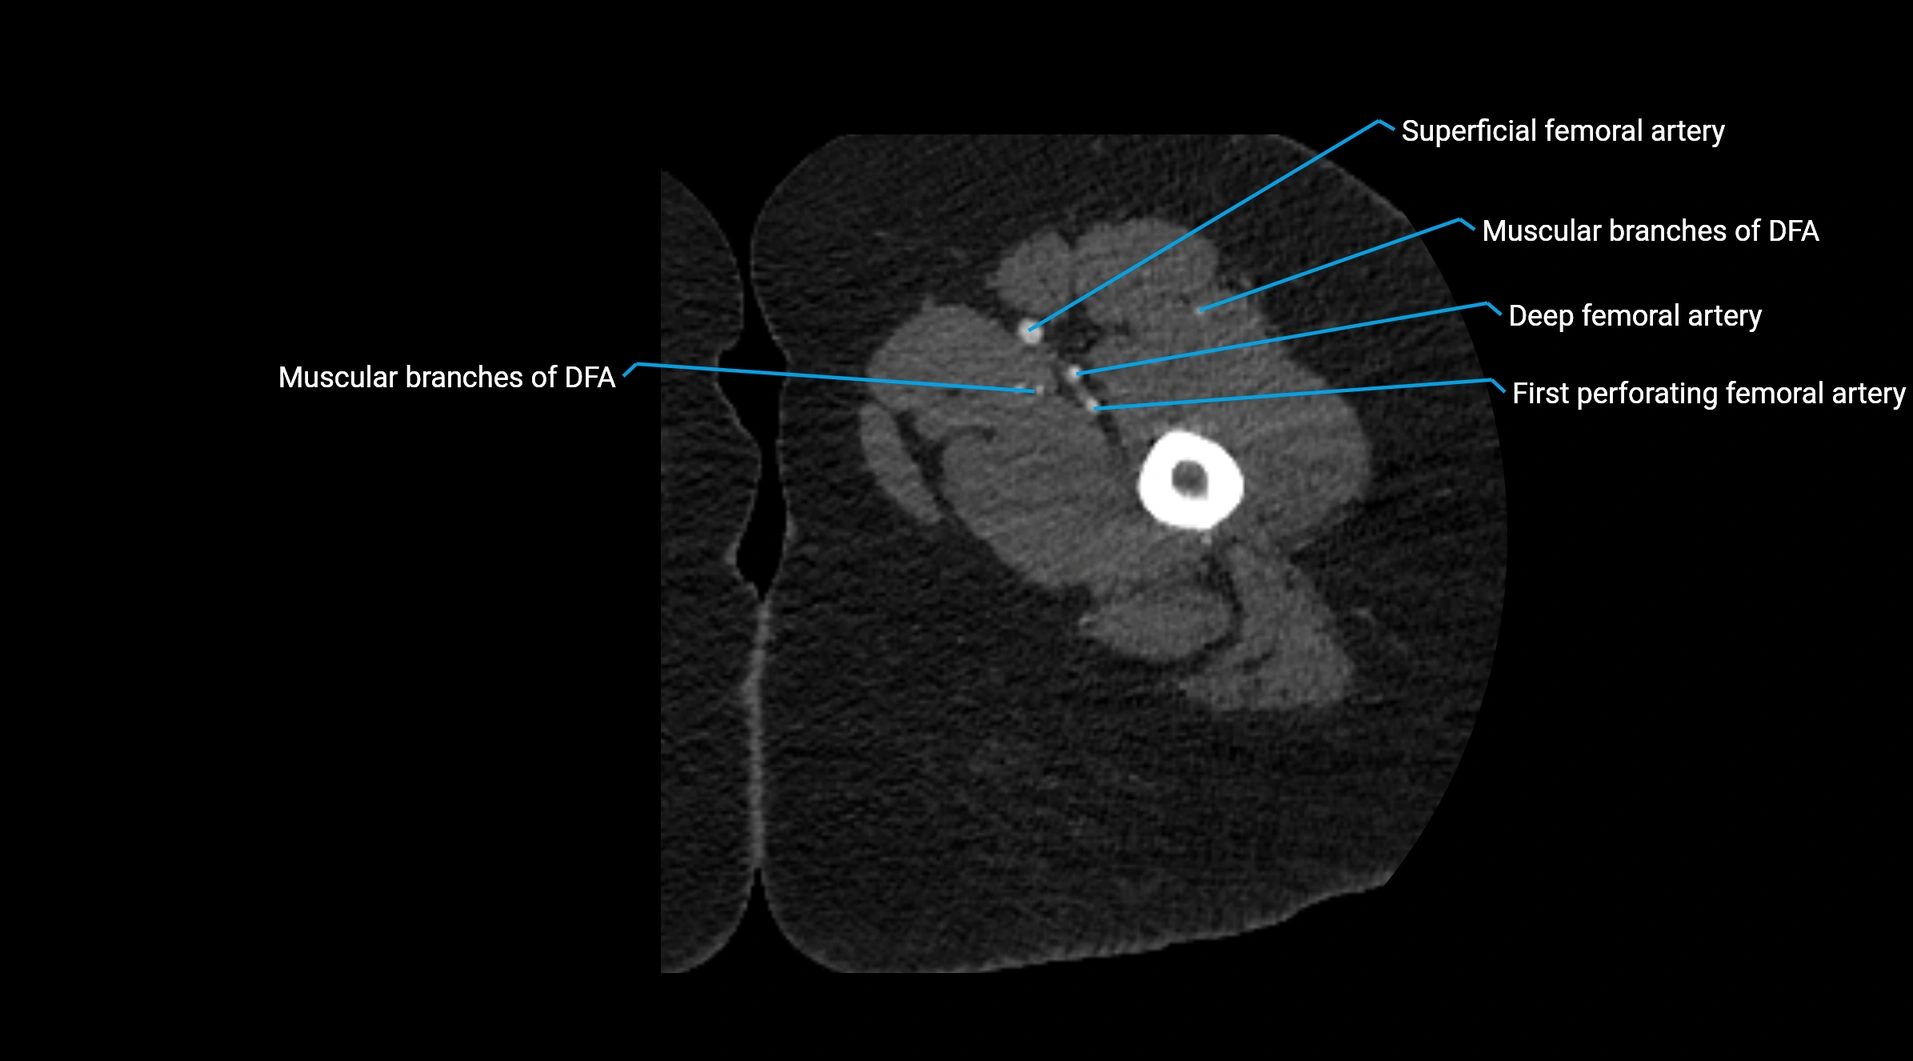

Contrast-enhanced CT (CTA):

• Gold standard for abdominal aortic imaging

• Provides excellent detail of lumen, wall, aneurysm, thrombus, and branch vessels

• Multiplanar and 3D reconstructions help in aneurysm measurement, stent graft planning, and dissection evaluation

• Detects acute rupture, traumatic injury, or occlusion with high sensitivity